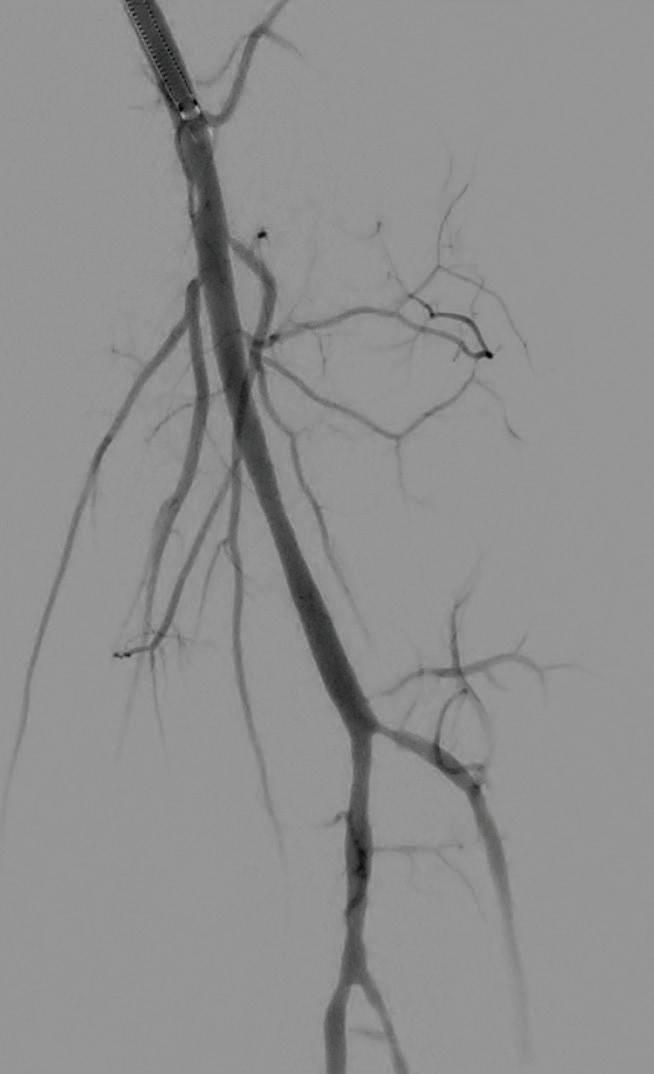

Post-intervention arteriogram

An excellent technical result was achieved. The SFA was widely patent with no significant residual stenosis. The posterior tibial and peroneal arteries were widely patent with brisk flow and no residual stenosis. Significantly improved flow was identified to the foot (Figure 4).